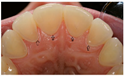

| Treatment Proposed | Upper Central Incisor n (%) | Upper Lateral Incisor n (%) | Upper First Molar n (%) | Upper Second Molar n (%) | Lower First Molar n (%) | Lower Second Molar n (%) |

| Dietary advice | 159 (80) | 154 (77) | 137 (69) | 124 (62) | 122 (61) | 122 (61) |

| Fluoride mouth rinse | 125 (63) | 120 (60) | 104 (52) | 93 (47) | 92 (46) | 91 (46) |

| Fluoride varnish | 100 (50) | 97 (49) | 91 (46) | 76 (38) | 62 (31) | 59 (30) |

| Application of adhesive | 19 (10) | 21 (11) | 20 (10) | 18 (9) | 11 (6) | 10 (5) |

| Resin infiltration | 39 (20) | 38 (19) | 23 (12) | 20 (10) | 21 (11) | 16 (8) |

| Application of flowable resin | 47 (24) | 50 (25) | 40 (20) | 35 (18) | 26 (13) | 27 (14) |

| Glass ionomer cement | 9 (5) | 10 (5) | 15 (8) | 13 (7) | 11 (6) | 10 (5) |

| Composite restoration | 57 (29) | 55 (28) | 65 (33) | 57 (29) | 65 (33) | 62 (31) |

| Onlay | 19 (10) | 20 (10) | 28 (14) | 23 (12) | 39 (20) | 44 (22) |

| Metal crown | 5 (3) | 6 (3) | 24 (12) | 22 (11) | 33 (17) | 34 (17) |